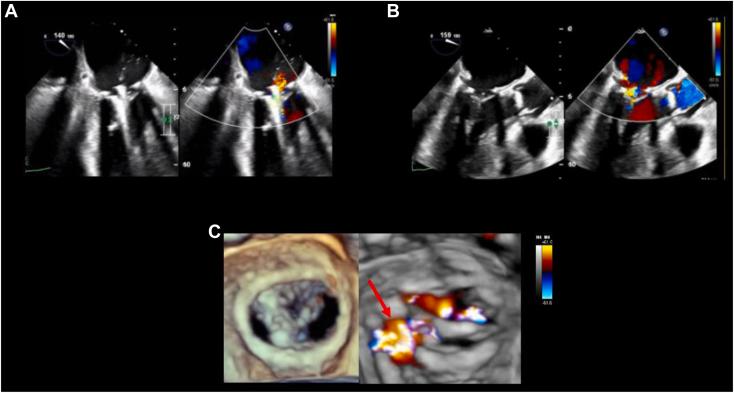

经食管超声心动图引导下二尖瓣环成形术后严重二尖瓣反流的经导管二尖瓣缘对缘修复:病例系列

Transesophageal Echocardiography Guidance during Transcatheter Mitral Valve Edge-to-Edge Repair for Severe Mitral Regurgitation Post-Mitral Annuloplasty: A Case Series.

• Redo surgery for severe MR after MA can be high risk. • m-TEER can be successful if patient is not a candidate for redo surgery or valve-in-ring. • Small mitral orifice area and postdevice mean gradient may limit m-TEER to 1 device. • We present 3 cases of m-TEER for severe MR after MA. • TEE guidance may optimize m-TEER success for severe MR after MA.

摘要

• 二尖瓣置换术后严重二尖瓣反流再次手术风险可能很高。

• 如果患者不适合再次手术或瓣膜环内植入瓣膜,经皮二尖瓣缘对缘修复术(m-TEER)可能会成功。

• 二尖瓣口面积小和装置植入后平均压差可能会将m-TEER限制为单次装置植入。

• 我们展示了3例二尖瓣置换术后严重二尖瓣反流行m-TEER的病例。

• 经食管超声心动图(TEE)引导可能会优化二尖瓣置换术后严重二尖瓣反流的m-TEER成功率。